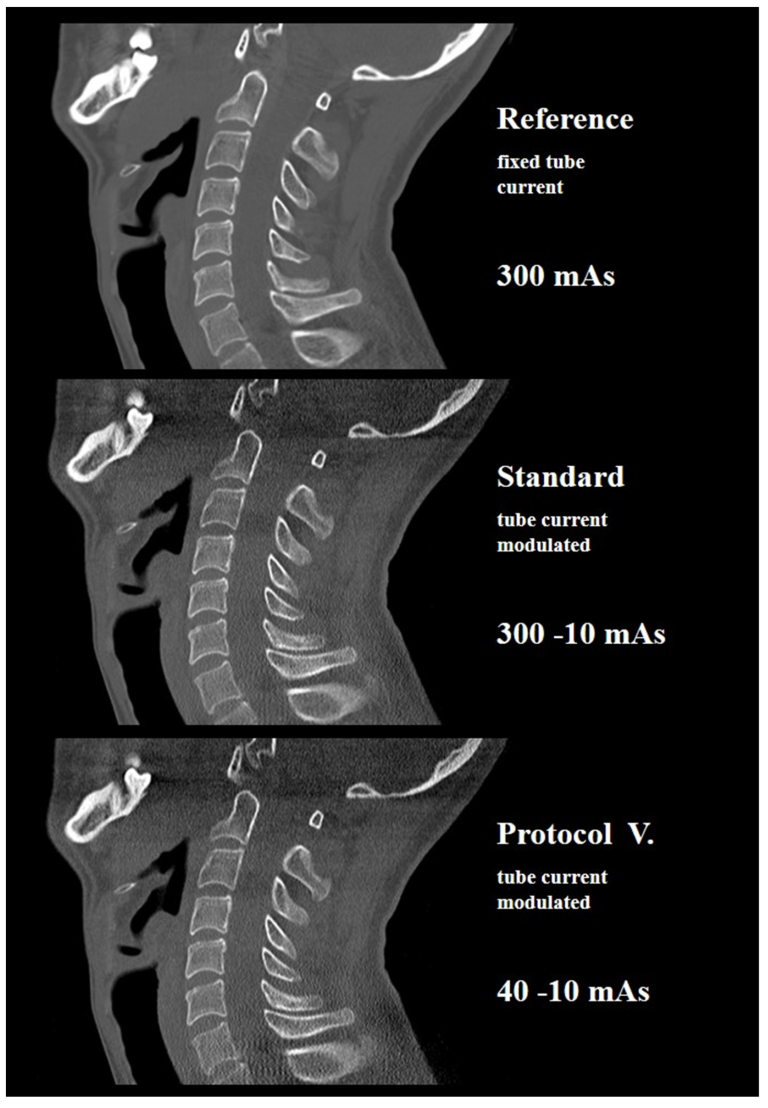

3.1. Cadaver Study

| VII. | 20 | 2.32 | V. | 40–10 | 2.60 ± 0.93 | 2.41 | 3.66 | 60 ± 21 | 49 | 76 | 0.31 ± 0.11 | 0.25 | 0.39 |